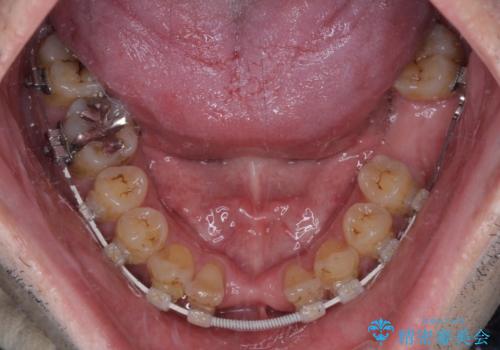

矯正治療を行いながら、欠損部はインプラントによる補綴治療を希望されたため、補助装置を用いたワイヤー矯正によりスペースを確保しながら歯列を整え、適宜インプラントを埋入していくこととしました。

在宅勤務のため、前歯にスペースが長期間できることに対して特に問題はないとおっしゃったため、スペースはそのままに治療を進めていくこととしました。